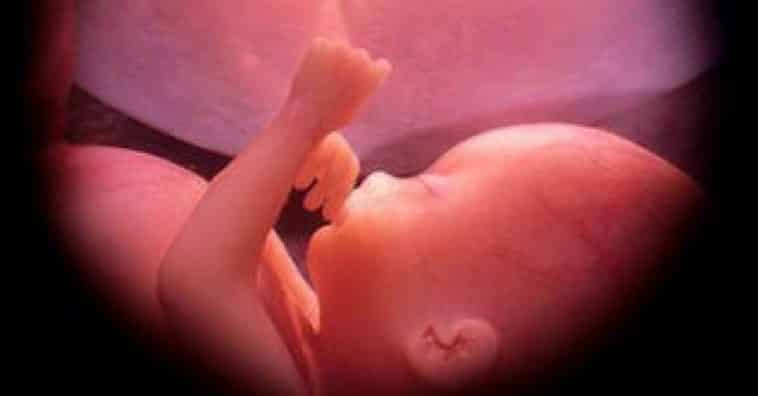

Aos 6 meses de gestação o bebê já está bem formado

E com 36 semanas está prestes a deixar o útero para iniciar uma jornada incrível no mundo externo